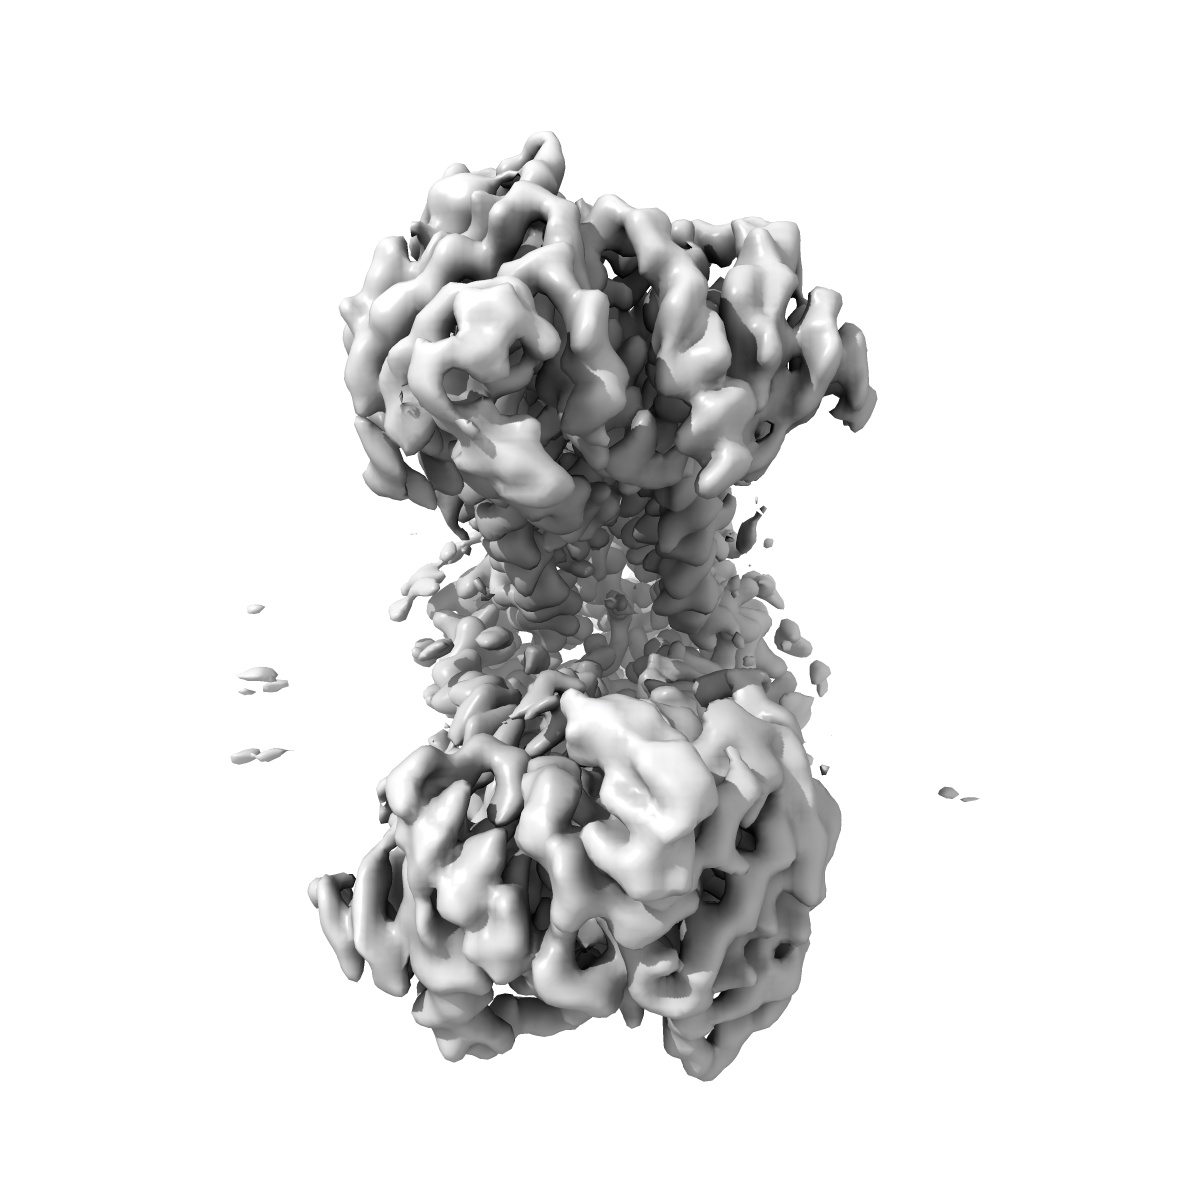

EMD-47987

BSEP Apo Structure in GDN

2.8 Å

Sample Organism: Homo sapiens

Sample: BSEP

Fitted models: 9ege

A structural and mechanistic model for BSEP dysfunction in PFIC2 cholestatic disease.

Gruget C, Reddy BG , Moore JM

(2025) Commun Biol , 8 , 531 - 531

PUBMED: 40195555

DOI: doi:10.1038/s42003-025-07908-0